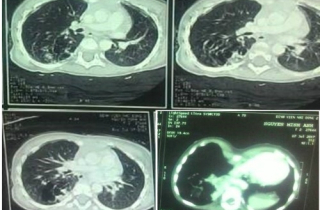

Bệnh viện Nhi đồng 2 lần đầu phẫu thuật nội soi lồng ngực cho bé gái hai tuổi, cắt bỏ thùy dưới phổi phải chứa...

Chia sẻ